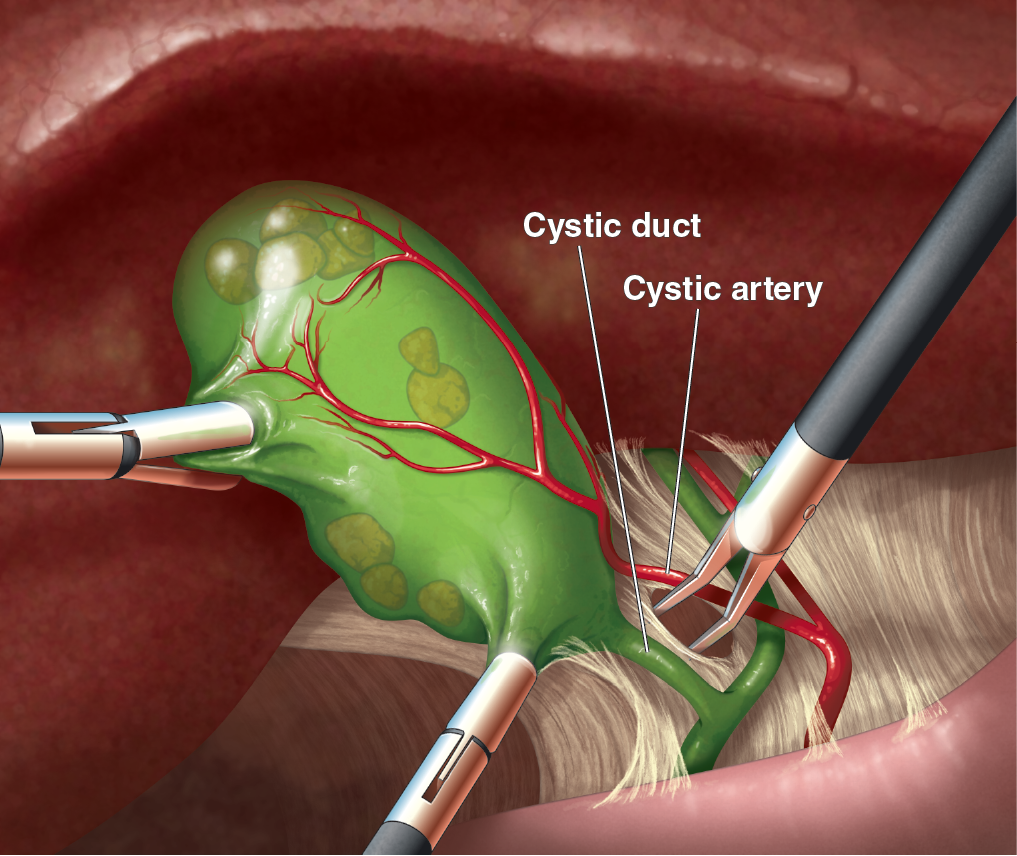

Medical Illustration

All images are works made for hire and are the exclusive property of the client. These are shown as sample purposes of my work only. For licensable work, please see my Illustration Services page.

Medical Illustrator for Precision Graphics, Lachina, and Human Kinetics Publishing (current)

Contract freelancer for many others, some examples of my work below.